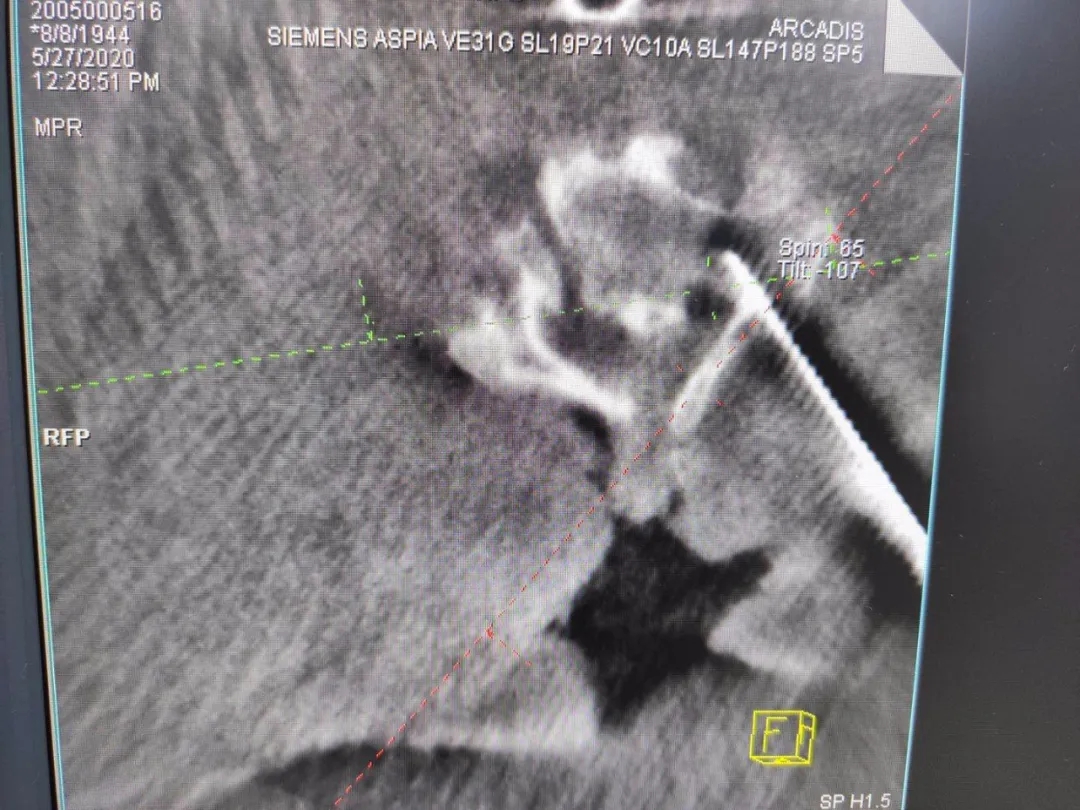

°´Éè¼Æ¾ÙÐÐÖÃÈëµ¼Õë

ÈýάÔÙ´ÎÑéÖ¤µ¼ÕëλÖ㬣¬£¬£¬£¬Öõ¼¾«×¼

ÔÚÌìçá?¹Ç¿ÆÊÖÊõ»úеÈ˸¨ÖúÏ£¬£¬£¬£¬£¬Í¨¹ý¾«×¼¶¨Î»£¬£¬£¬£¬£¬Ò½ÉúΪ·¶°¢ÆÅÖÃÈëÂݶ¤£¬£¬£¬£¬£¬ÊÖÊõÖмÈûÓÐËðÉ˵½×µ¶¯ÂöҲûÓÐÅö´¥¼¹Ë裬£¬£¬£¬£¬ÊÖÊõǰºóÖ»ÓÃÁËÒ»¸ö°ëСʱ£¬£¬£¬£¬£¬³öѪÁ¿ºÜÊÇÉÙ¡£¡£¡£¡£¡£¡£¡£